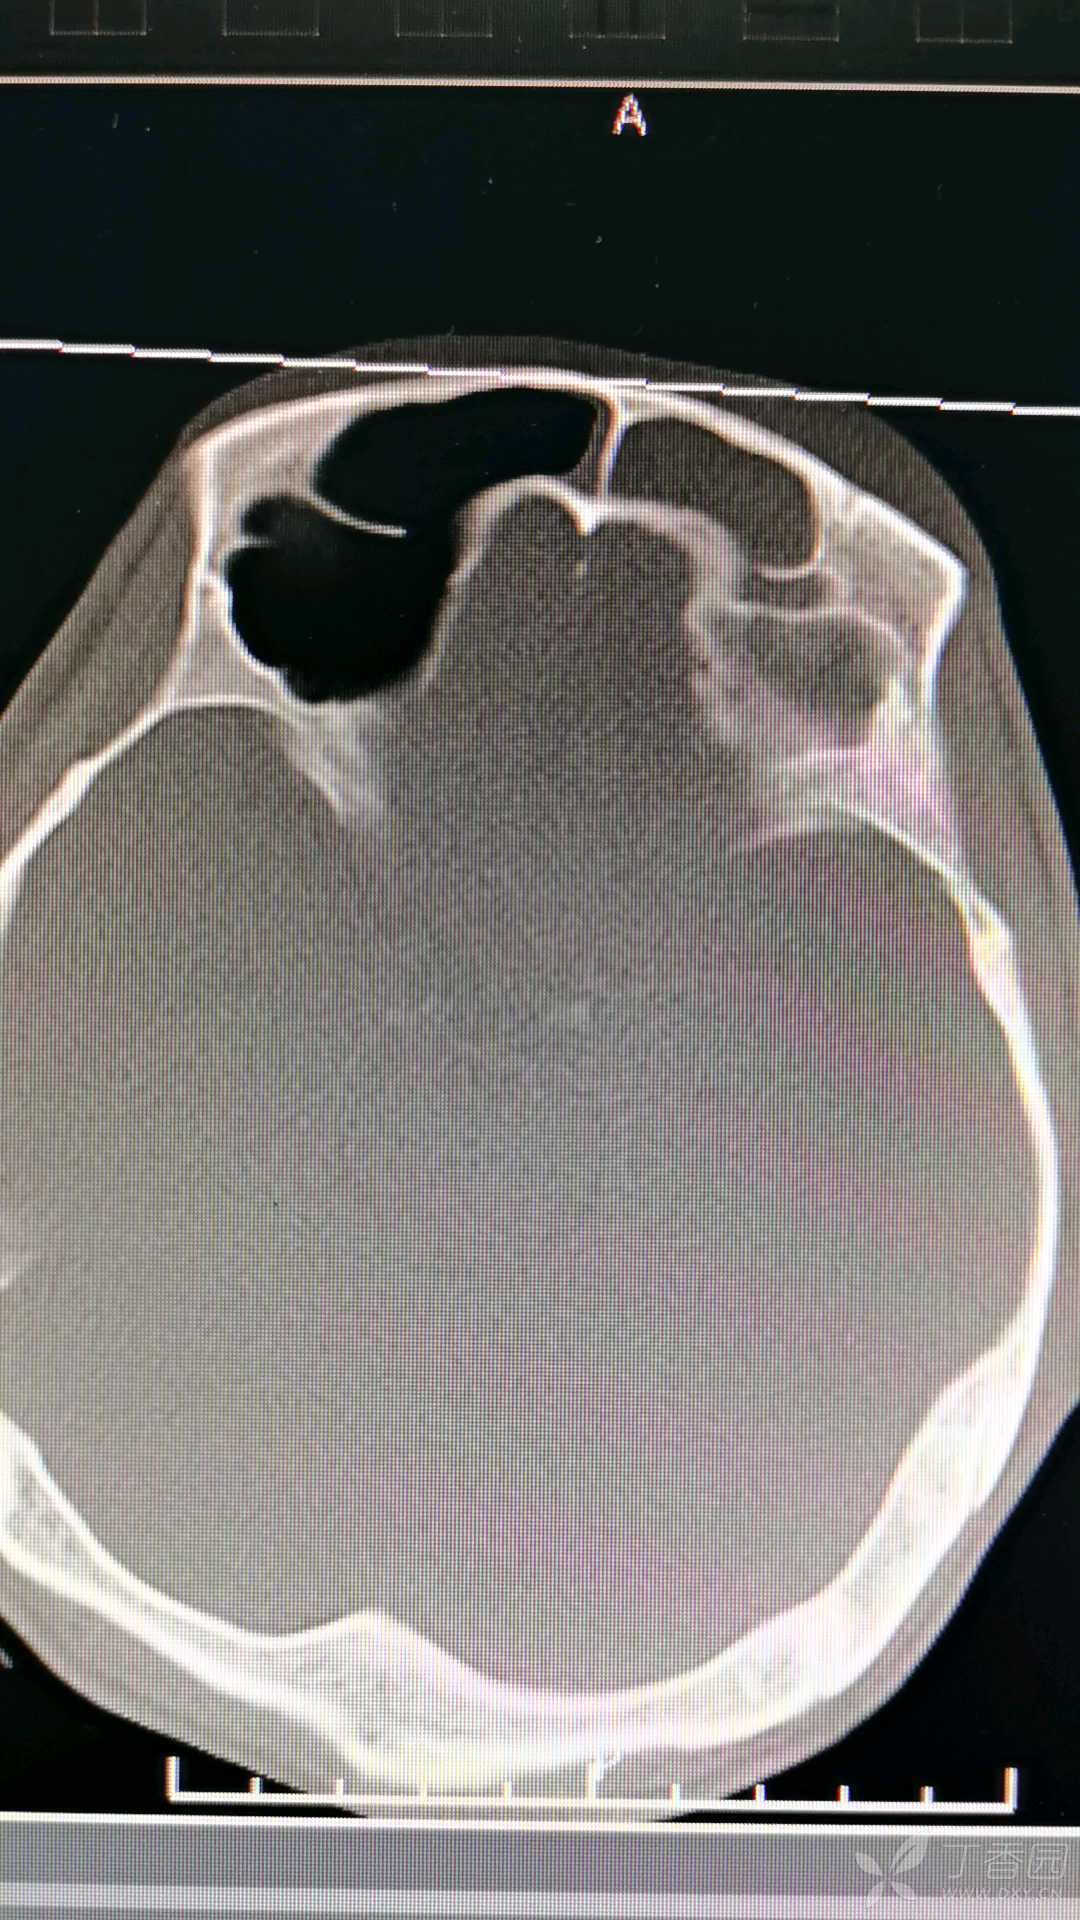

截取关键层面。两次大概在同一水平上。

入院截取